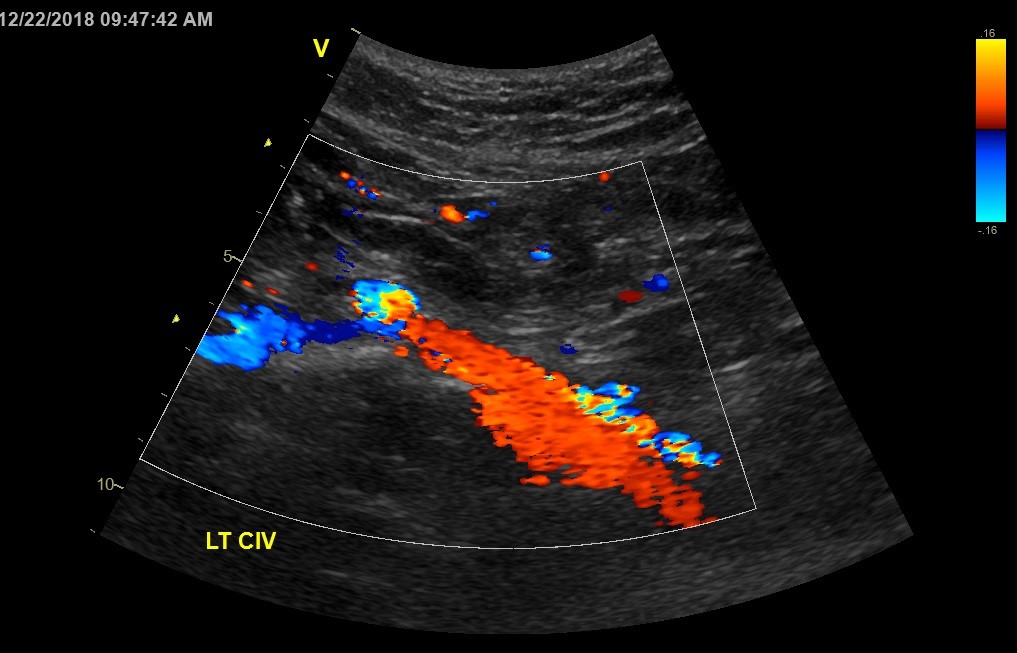

From jetem.org

A Case Report of MayThurner Syndrome Identified on Abdominal Turners Syndrome On Ultrasound Certain features on an ultrasound image may raise suspicion that your baby has turner syndrome or another genetic condition. The diagnosis requires confirmation after. Turner syndrome (ts) is a common sex chromosome disorder, with a varied clinical spectrum and prognosis. Lymphoedema, a condition that causes swelling in the body's tissues, can affect unborn babies with turner syndrome, and may be. Turners Syndrome On Ultrasound.

From www.pocus.org

MayThurner Syndrome (MTS) PointofCare Ultrasound Certification Academy Turners Syndrome On Ultrasound An amniocentesis or chorionic villus sampling is required for a definitive prenatal diagnosis of turner syndrome and to confirm monosomy of the x chromosome. Turner syndrome should be suspected when a prenatal ultrasound shows fetal hydrops, cystic hygroma, or cardiac defects. Turner syndrome (ts) is a common sex chromosome disorder, with a varied clinical spectrum and prognosis. It may range. Turners Syndrome On Ultrasound.